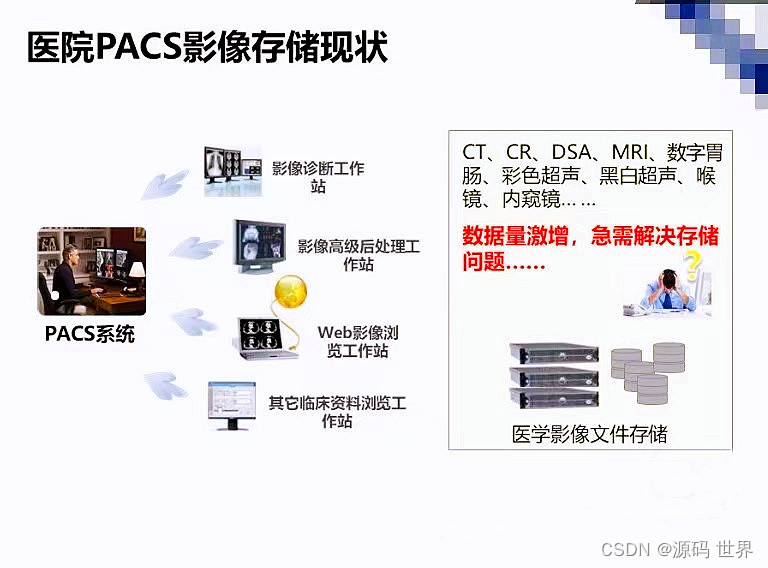

PACS系统的作用

影像归档与通信系统(PACS)则专注于影像资料的存储、检索、分发和通信。PACS系统可以联接不同的影像设备(如CT、MR、XRAY、超声、核医学等),存储和管理图像,以及图像的调用与后处理。PACS系统也可以与其他系统如HIS、RIS集成,以提高工作效率和检查准确性。

由于我国开发和引进PACS系统较晚,目前已经建立并有效运行的PACS系统并不多见(特别是内陆省市)。究其原因主要是标准化程度低、兼容性差,一般为封闭式的专用系统,既不经济、价格也昂贵,配置的硬件不够合理,对工作量大的医院缺乏强大的存储子系统,无法支持数据量巨大的常规放射影像,因此不能真正实现“无片化”管理。多数PACS系统也没有其有效的工作流程和自动化管理功能,也不能向临床诊断提供所需的全部,表现在在线信息少,响应速度慢。对网络安全、保密和符合法律要求方面还不可靠。